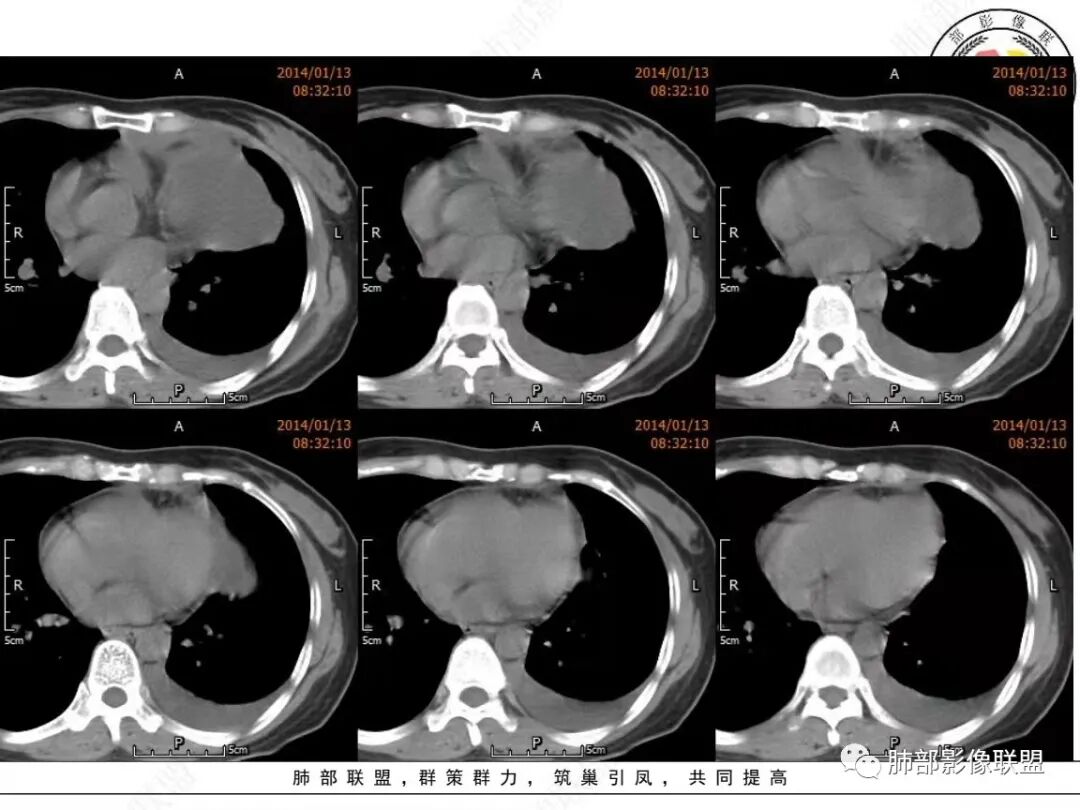

真人:中老年女性,左前纵隔囊实性占位,边界比较清晰,肺组织受压改变,考虑良性病变,囊性胸腺瘤?鉴别囊性畸胎瘤

宇宙:左前中纵隔囊性肿块伴壁结节,结节强化,边缘光整,邻近血管及左侧支气管受压,左侧胸水,考虑囊性胸腺瘤

邢瑞欣:老年女性,定位前纵隔,近圆形囊性低密度影,壁厚有软组织影,强化明显,定性良性肿瘤,囊性畸胎瘤,囊肿,鉴别,转移瘤,胸腺瘤

空格:病灶的后内下增厚的包膜未见连续,纵隔脂肪浑浊密度增高、左侧胸腔积液,开始出现前胸后背的疼痛,完全可以用囊性灶破裂,引起化学刺激来解释。  不然看着软趴趴的病灶,既不可能是转移或侵犯胸膜引起的积液,也不像单纯纵隔或胸腺脓肿,因为白细胞不高。囊肿破裂是最好的解释。  这点就是手术指征。   定性  良性。    分析下来源:  1 这个部位常见的囊实性病灶有 囊性畸胎瘤、胸腺瘤出血囊变、支气管囊肿伴感染,淋巴管来源(前无神、后无皮,神经源性肿瘤不用考虑)。从发病年龄看,胸腺瘤>畸胎瘤,从壁结节强化后面丝丝拉拉的强化看,畸胎瘤可能大。两者都可以接受。综合囊性畸胎瘤破裂大于胸腺瘤出血囊变

衡妈:老年女性,定位是关键。左前中纵隔囊实性占位,囊性为主,囊壁厚薄不均,局部内壁可见壁结节,增强中等强化。考虑囊性畸胎瘤,鉴别胸腺瘤。